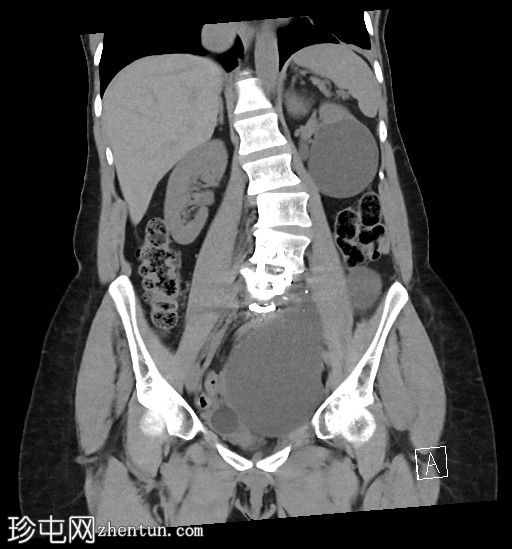

左侧腹膜后可见一巨大囊性肿块,位于左侧腰大肌内侧,紧邻多个手术夹(ALIF手术所用),这些手术夹紧贴囊性肿块后壁。

膀胱已行引流管减压,并被囊性肿块向右侧推移。

子宫和左侧附件在囊性肿块前方保持正常的脂肪间隙,因此附件囊性病变的可能性较小。

左侧输尿管难以辨认,因为它位于囊性肿块下缘后方。

左侧腹膜后巨大囊性病变,符合术后淋巴囊肿。鉴别诊断包括血清肿、尿瘤和脑脊液积聚,但脑脊液积聚的可能性较小。